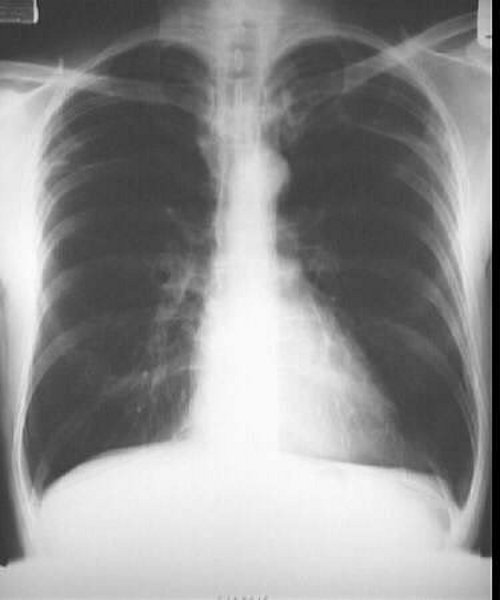

La malattia polmonare ostruttiva cronica, identificata dall’acronimo inglese COPD e da quello italiano BPCO (broncopneumopatia cronica ostruttiva), si riferisce a quel gruppo di malattie che causano il blocco del flusso d’aria nei polmoni e provocano problemi respiratori. Tra di queste alcune sono l’enfisema, la bronchite cronica e l’asma.

La bronchite è causata dall’irritazione e dall’infiammazione dei bronchi, i canali attraverso cui l’aria passa nei polmoni. Quando avviene l’infiammazione, i bronchi si riempiono di muco, provocando generalmente accessi di tosse.